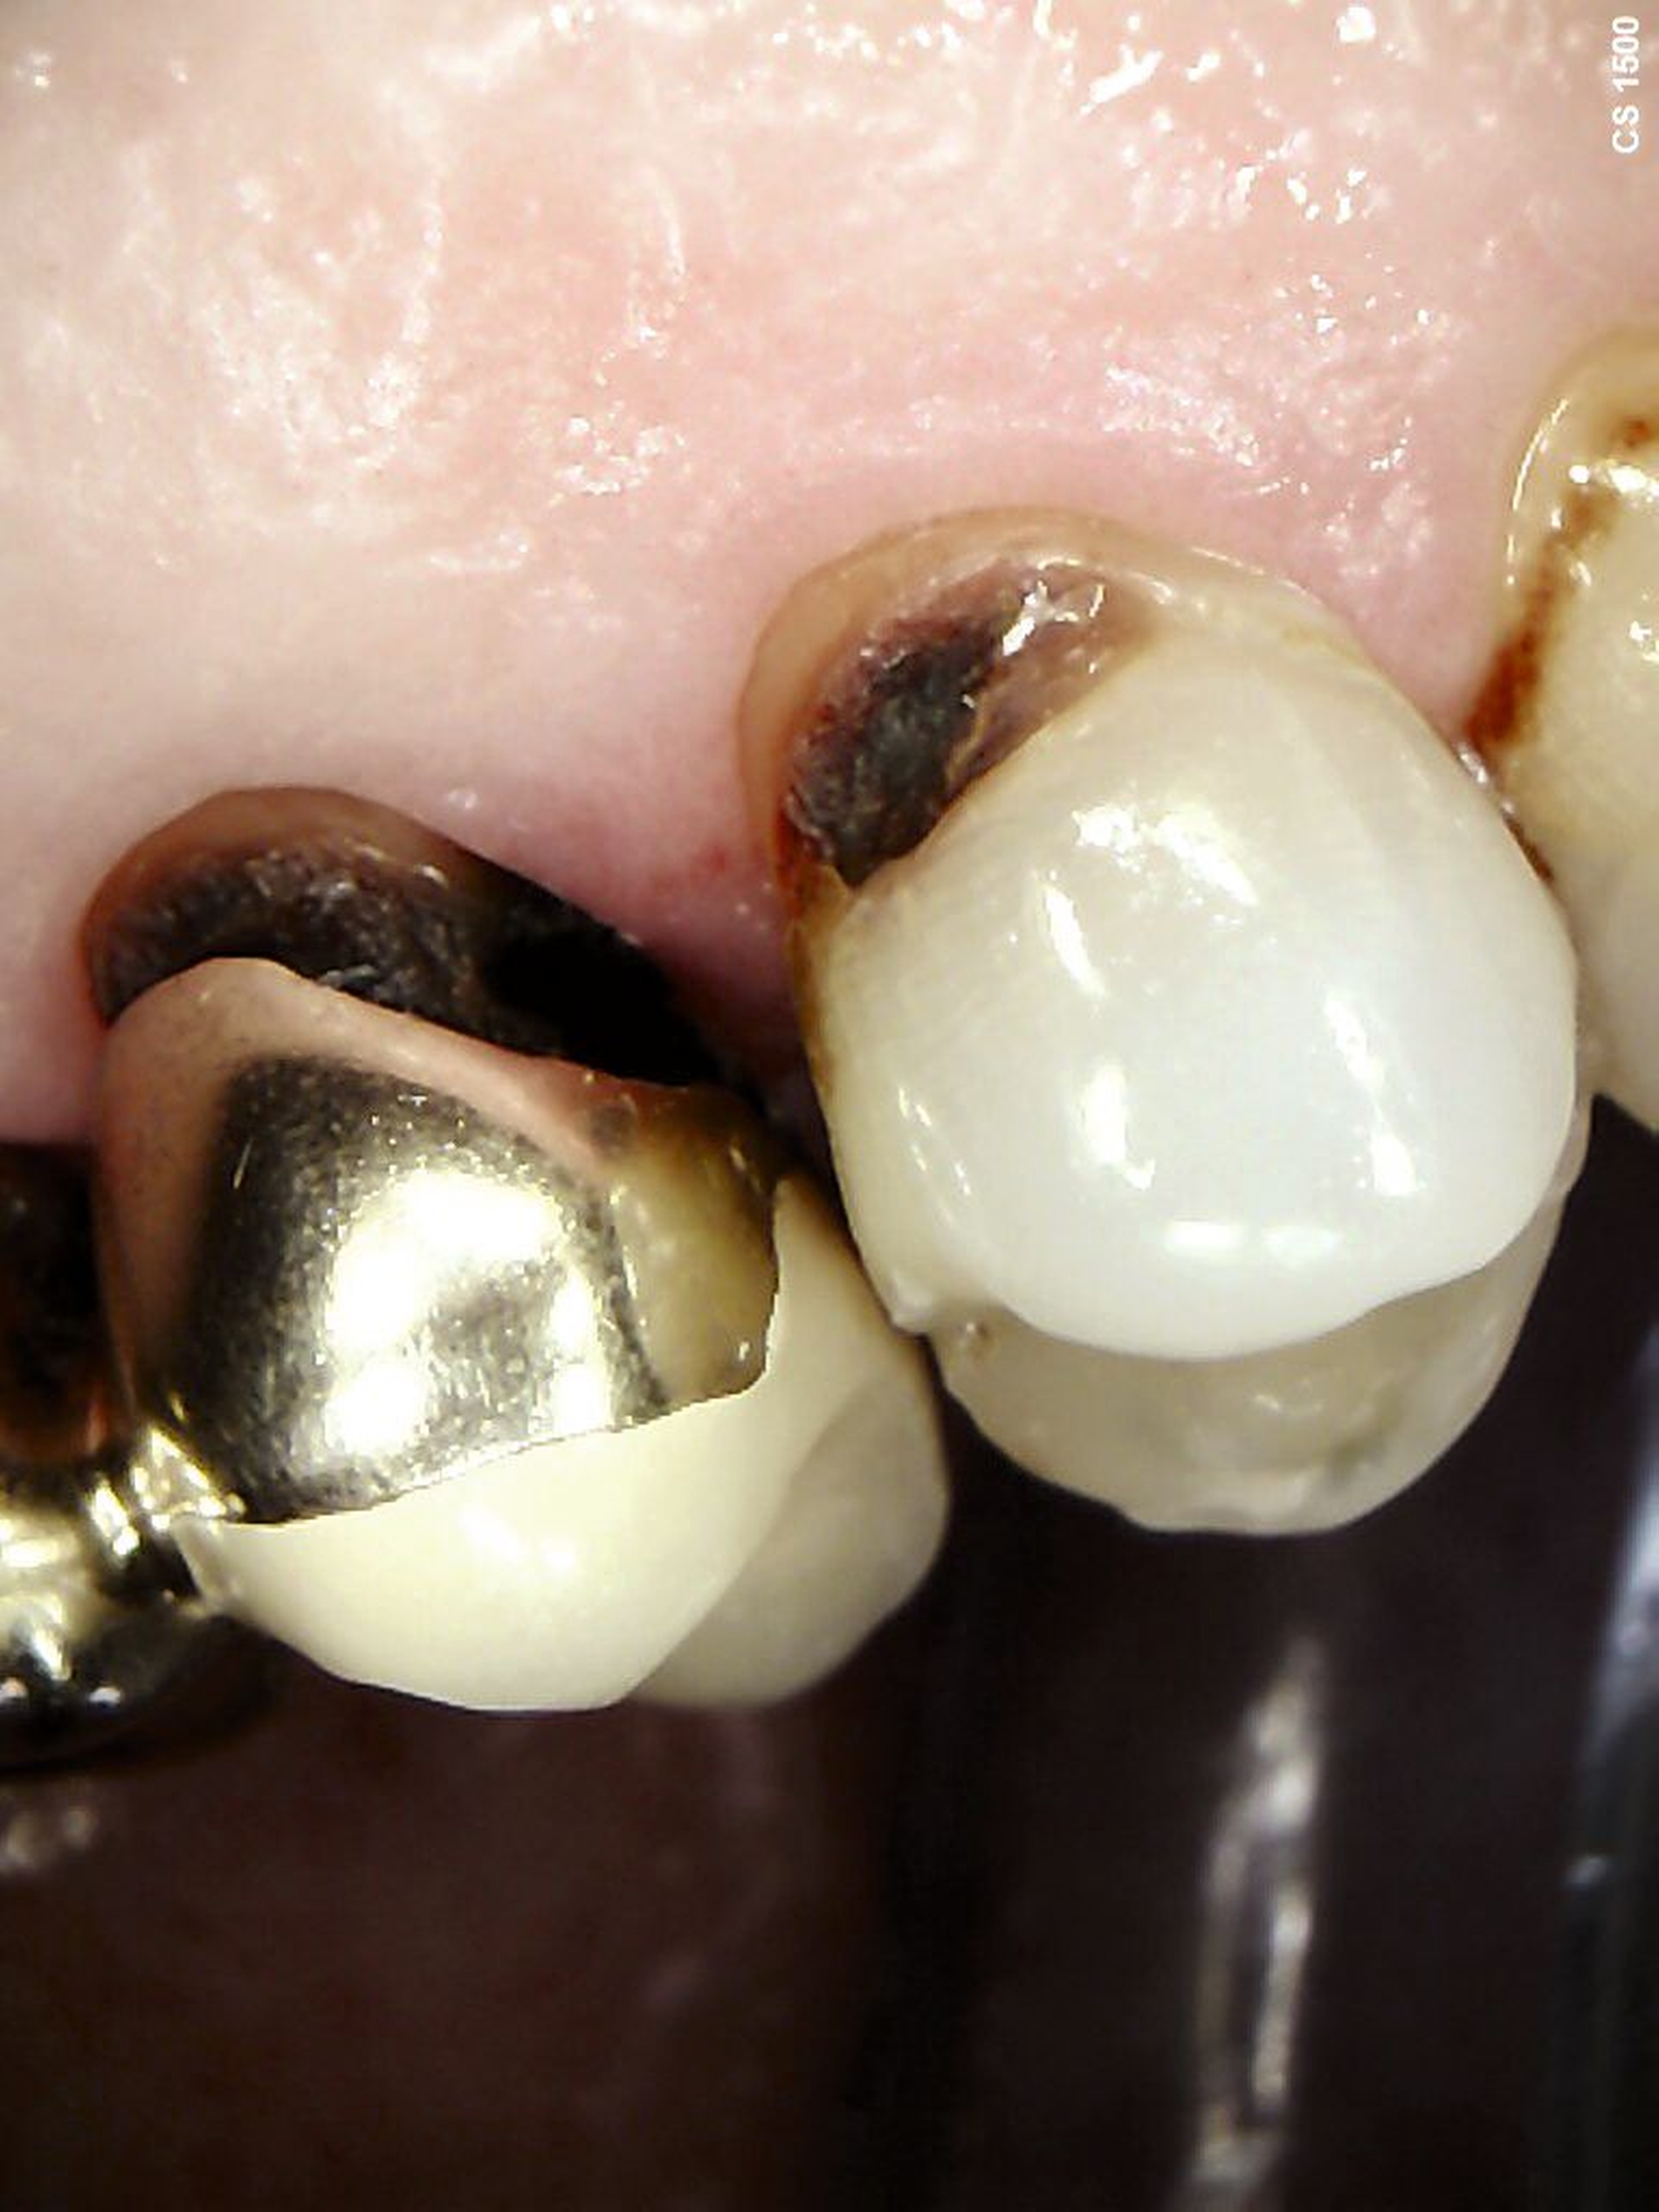

Eine bekannte Nebenwirkung bei Anwendung auf kariösen Läsionen ist die Schwarzfärbung des behandelten Bereichs (Abbildungen 3, 4). Verfärbungen können aber auch bei Applikation auf kariesfreien Wurzeloberflächen entstehen, diese sind jedoch mit einer professionellen Zahnreinigung gut zu entfernen (Abbildung 2).

Tatsächlich zeigt die klinische Erfahrung, dass es möglich ist, bei mehrmaliger Applikation innerhalb eines Vierteljahrs auch sehr aktive Läsionen mit taktil weicher Oberfläche trotz eingeschränkter Mundhygiene gut zu erhärten (Abbildung 4). Für die koronale Karies bei Kindern konnte die bessere Wirkung nach wiederholter Anwendung allerdings nicht bestätigt werden. [Smutkeeree et al., 2025].

Der Wirkungsmechanismus ist bislang nicht aufgeklärt. Die wesentlichen Verbindungen in SDF-behandelten Läsionen sind Silberphosphat, Silberoxid und Silbersulfid. Silberphosphat ist ein guter Photokatalysator [Yi et al., 2010], der spezifische chemische Reaktionen mit oder zwischen den verschiedenen beteiligten Verbindungen und Zahnstrukturen induzieren oder aber die auch ohne Licht eintretenden Reaktionen einfach beschleunigen könnte. Es wird vermutet, dass beispielsweise metallische Silbernanopartikel entstehen könnten [Li et al., 2019]. Abbildung 3 zeigt bräunliche Verfärbungen der Schleimhaut nach Lichteinwirkung.